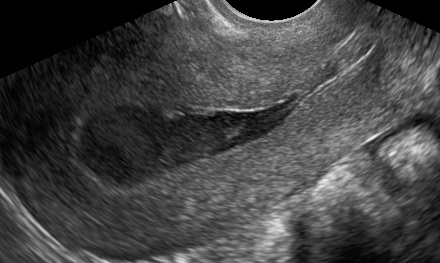

HomeGynecology Gynecology Vaginal Inclusion Cyst Laparotomy for Giant Ovarian Tumor Fallopian Tube Torsion Vesicovaginal fistula after hysterectomy Parasitic Myoma Smooth Muscle Tumor of Uncertain Malignant Potential (STUMP) Mucinous Cystadenoma Hysteroscopic Myomectomy Laparoscopic Excision of a Mesothelial Cyst of the Uterus Laparoscopic Treatment of A Chronic Ectopic Pregnancy Laparoscopic Removal of an intraabdominal IUD Paraovarian / Paratubal Cyst LAparoscopic Supracervical Hysterectomy (LASH) Laparoscopic Myomectomy Laparoscopic Management of Tubal Ectopic Pregnancy #2 Salpingectomy Laparoscopic Management of Tubal Ectopic Pregnancy #1 Salpingotomy Masterclass – Ultrasound Study of the Tubal Ectopic Pregnancy Total Laparoscopic Hysterectomy (TLH) Laparoscopic Management of an Immature Teratoma Ultrasound Study of Borderline Ovarian Tumors Laparoscopic Bilateral Salpingectomy: Tips & Tricks Transcervical Resection of the Endometrium Ultrasound Study of Cervical Cancer Pelvic Lymphoma Ureterovaginal fistula after hysterectomy Adenomyosis How to optimize your ultrasound image Hematometra after conization Endometrial Cancer Hemoperitoneum Endometrioma Infectious non-puerperal mastitis Hydrosalpinx Adnexal torsion Deep infiltrating endometriosis Struma ovarii Caesarean scar pregnancy Interstitial pregnancy Cervical pregnancy Share this: Share on X (Opens in new window) X Share on Facebook (Opens in new window) Facebook Share on LinkedIn (Opens in new window) LinkedIn